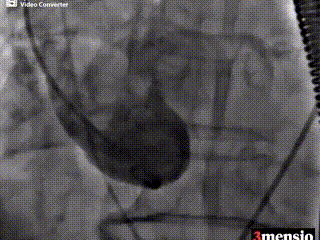

术后DSA影像